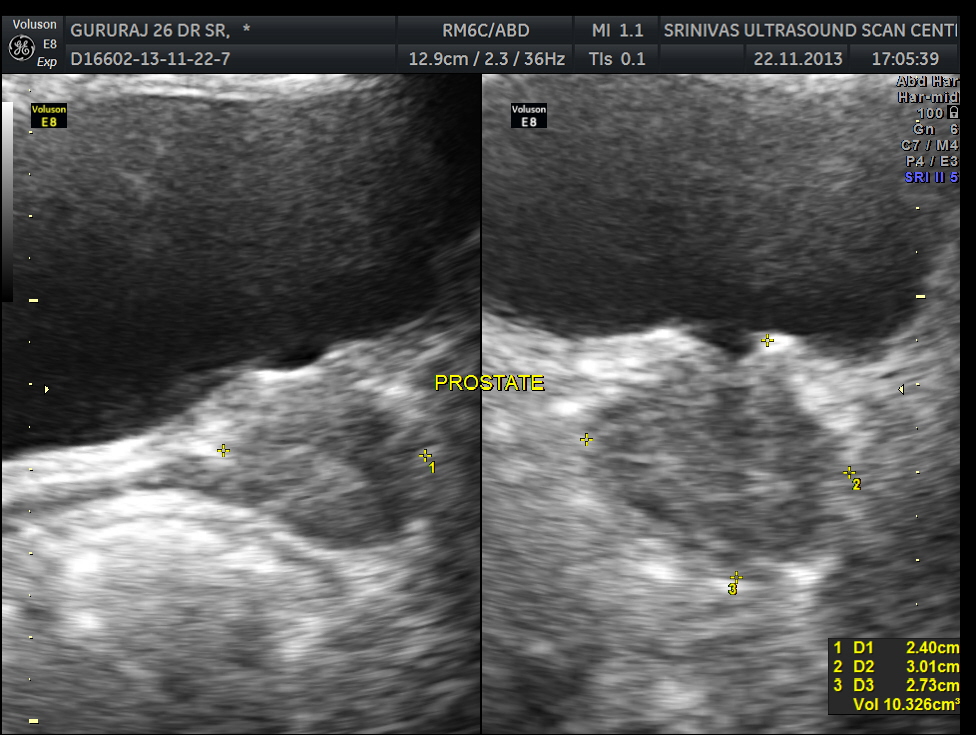

An ultrasound abdomen was done as part of evaluation of anemia.

This was a 27 year old man working as an I.T.consultant in a city. He started getting headaches , which were disabling . The headache was mostly one sided . He was evaluated for the headache ; His CT scan of the brain was normal. He had features of iron defeciency anemia with thrombocytosis . His neurologist after a bit of trial and error made a diagnosis of ‘ indomethacin sensitive chronic paroxysmal hemicranial headache ‘ . He responded very well to indomethacin . But his anemia was not improving with medical treatment.